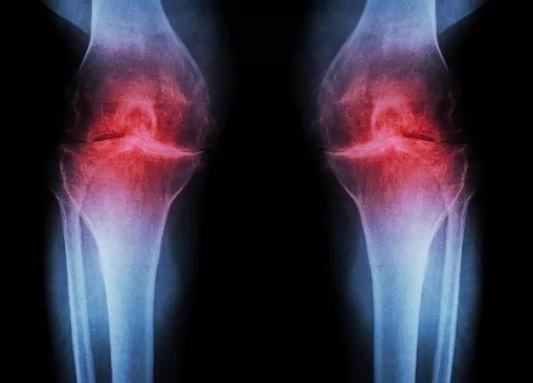

دواء جديد يعيد بناء غضروف الركبة ويعالج سبب الفصال العظمي

يُعد الفصال العظمي في الركبة من أكثر أسباب الألم المزمن والإعاقة شيوعا حول العالم، خاصة مع التقدم في العمر أو نتيجة الإصابات والأحمال الزائدة لدى الرياضيين. وعلى مدى عقود، انحصرت خيارات العلاج بين تخفيف الأعراض بالأدوية أو اللجوء إلى الجراحة واستبدال المفصل.